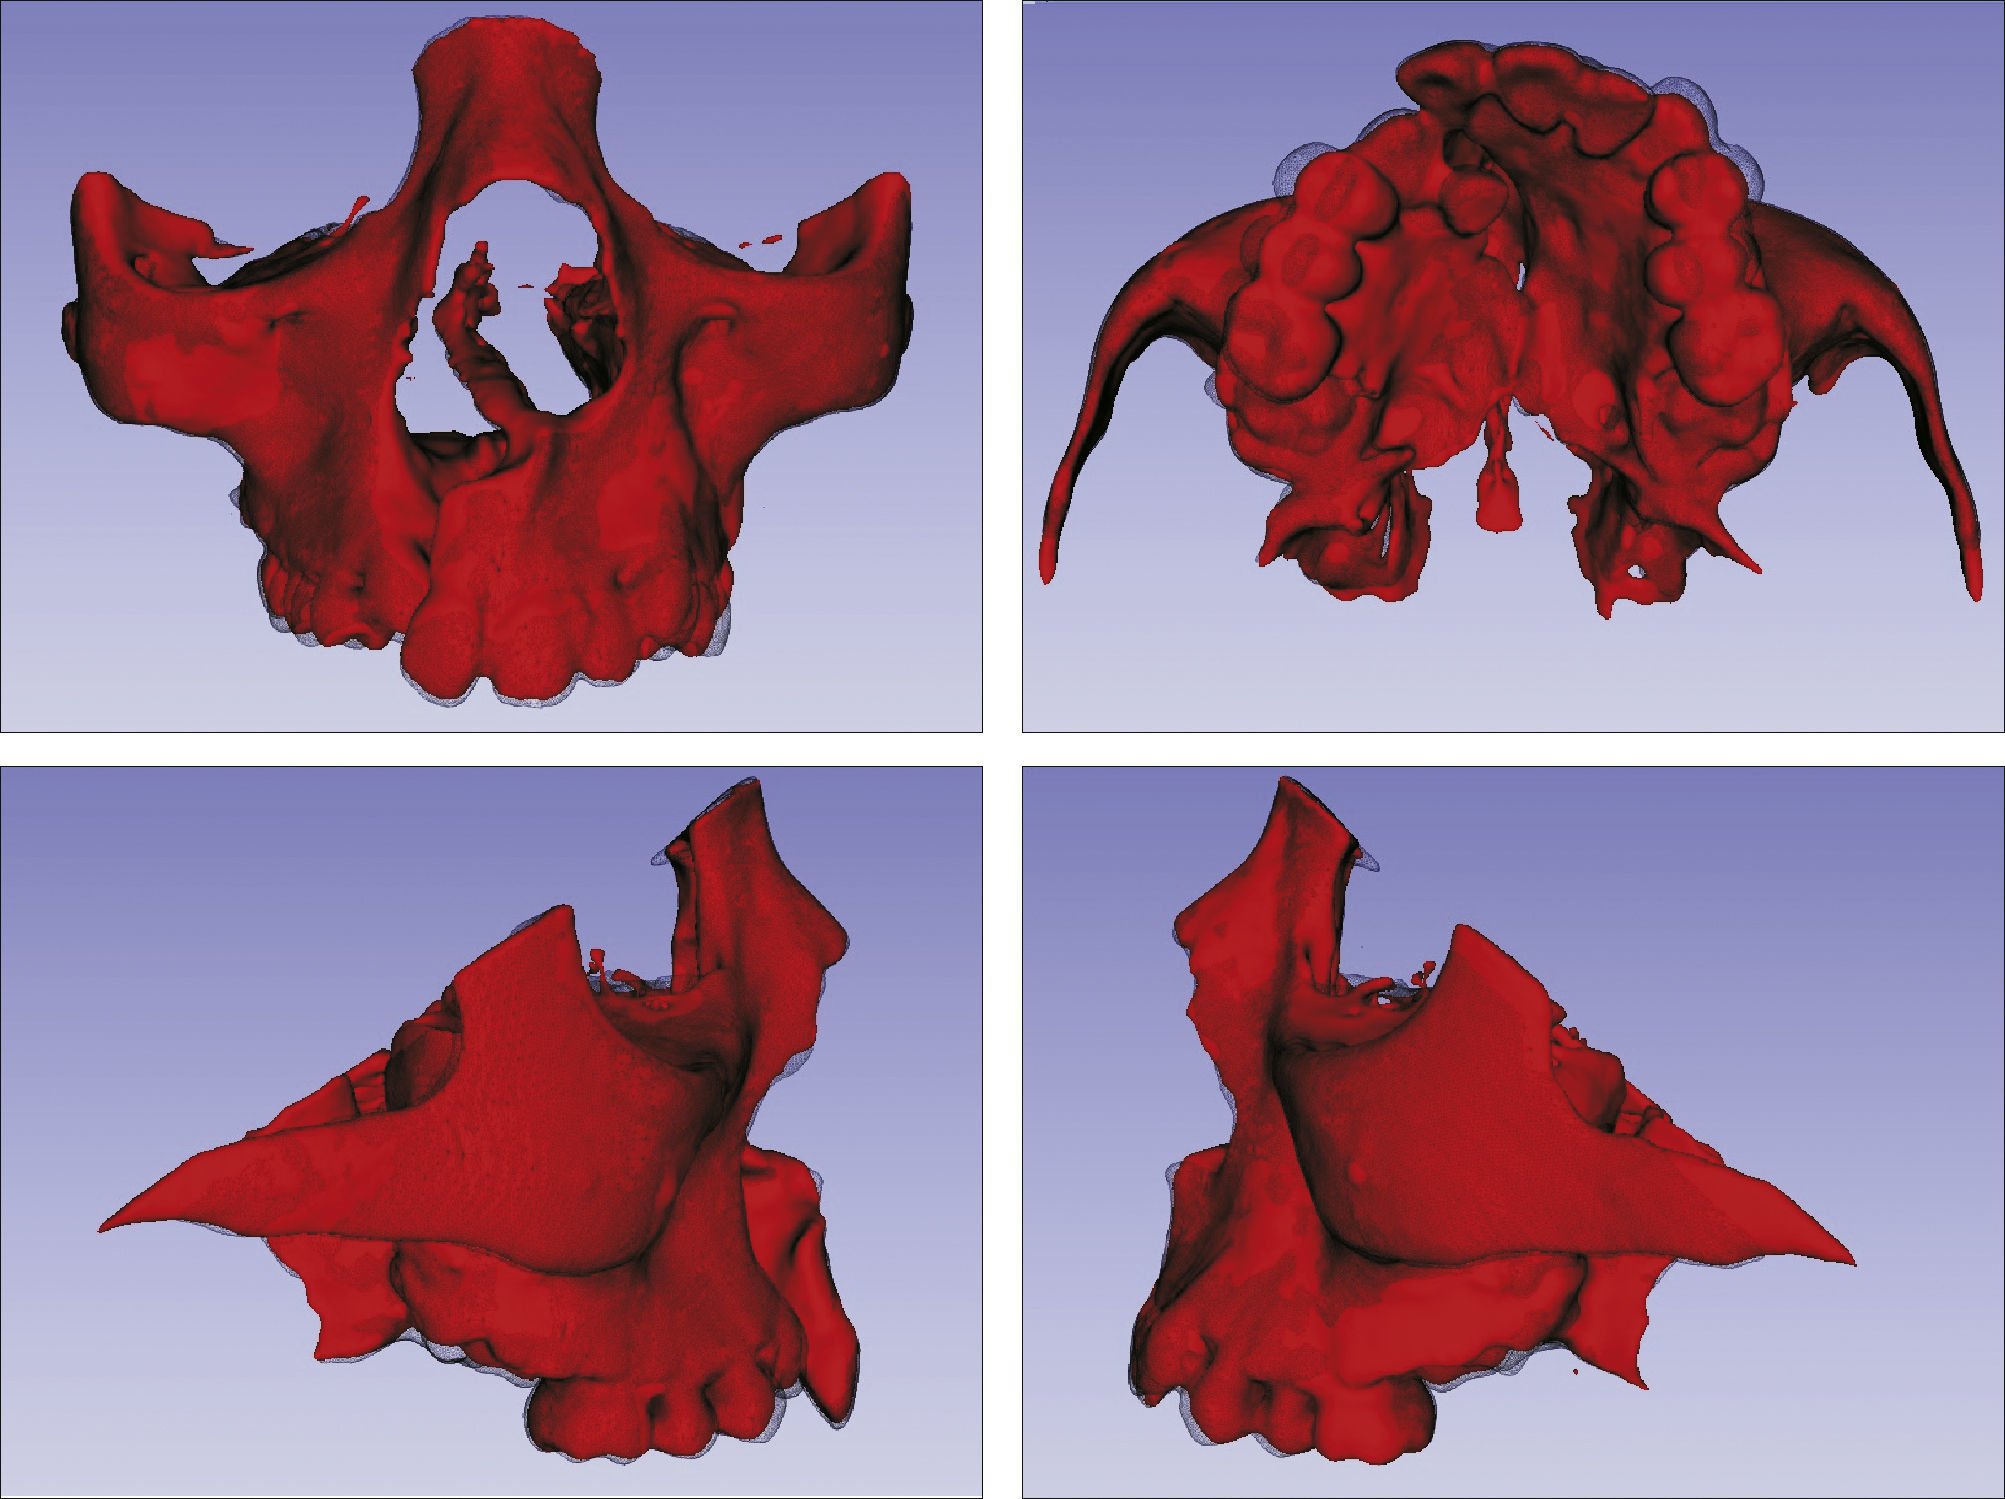

O surgimento e o aumento da acessibilidade da TCFC agregaram uma maior credibilidade ao diagnóstico clínico e às investigações científicas no estudo das deformidades craniofaciais19. Todavia, as informações 3D fornecidas pelas TCFC ainda vêm sendo rotineiramente analisadas de forma 2D, por medidas lineares em cortes ortogonais5,20. A construção e sobreposição de modelos virtuais 3D ainda é uma metodologia pouco difundida. Este estudo é um dos pioneiros que utiliza este método para avaliação de ERM em pacientes com fenda. A sobreposição baseia‐se na construção dos modelos virtuais 3D, utilizando o software SLICER21, pelos arquivos obtidos na TCFC, seguida pela sua justaposição, que utiliza a base do crânio como referência e a final obtenção dos métodos de medidas intitulados: sobreposição por semitransparência e mapa por códigos de cores22. A sobreposição por semitransparência revela uma análise qualitativa, em que o momento pós‐tratamento é retratado por uma malha preta translúcida, sobre o modelo inicial em vermelho (figs. 9 e 10). O aparelho em leque demonstrou um deslocamento de quase todos os dentes para vestibular e uma movimentação vestíbulo‐posterior do segmento menor (lado esquerdo [fig. 9]). O mapa por códigos de cores permite um complemento da análise visual, sendo que cada cor reflete uma alteração na posição das estruturas: azul – recuo; verde – estabilidade e vermelho – expansão. A intensidade da cor está diretamente relacionada à quantidade de movimentação. Todo o mapa é seguido por uma escala, com os valores em milímetros para cada cor (figs. 11 e 12). A observação feita na sobreposição por semitransparência do expansor em leque é confirmada no mapa por código de cores e nas medidas lineares. Uma menor porção de vermelho é visualizada em molares, quando comparada aos pré‐molares. O deslocamento para posterior e vestibular do menor segmento é constatado pela presença de azul na mesial dos dentes e vermelho nas eminências alveolares do lado em questão. Diferentes tonalidades de azul são vistas na cervical dos incisivos, possivelmente uma retroinclinação em decorrência da ausência de apoio mecânico no local. Para a quantificação das mudanças no posicionamento dentário, primeiramente identificou‐se, nos 3 cortes ortogonais, os pontos de referência para a medida (ponta da cúspide mésio vestibular dos primeiros molares superiores e ponta da cúspide dos caninos), tanto do lado direito como do lado esquerdo, utilizando o software ITK Snap23. Os pontos foram marcados com uma esfera de 0,5mm de diâmetro, identificando a posição 3D destas referências no espaço (fig. 13). A aferição das distâncias Euclidianas entre as esferas foi realizada com o auxílio da ferramenta Q3DC no programa SLICER23. O paciente A obteve um aumento de 3mm na distância intercanina e de 6mm na distância intermolar. Na elucidação do paciente que utilizou o disjuntor mini‐Hyrax invertido com BTP (B), observa‐se na sobreposição por semitransparência um deslocamento vestibular, principalmente dos pré‐molares e uma constância das demais áreas, achados corroborados no mapa por código de cores. A área que não está verde é a região de pré‐molares, vermelho por vestibular e azul por palatino, notando uma tonalidade entre verde e vermelho (amarelo) no corpo da maxila do lado menor (esquerdo). A oclusal dos molares, em vermelho, representa a erupção dos elementos.

Sobreposição com semitransparência dos modelos 3D do tratamento com o aparelho mini‐Hyrax invertido com BTP. Antes da expansão representado por vermelho e após a expansão pela malha fina translúcida. Observa‐se um trespasse da malha preta para vestibular na região dos pré‐molares, indicando expansão concentrada nessa região.